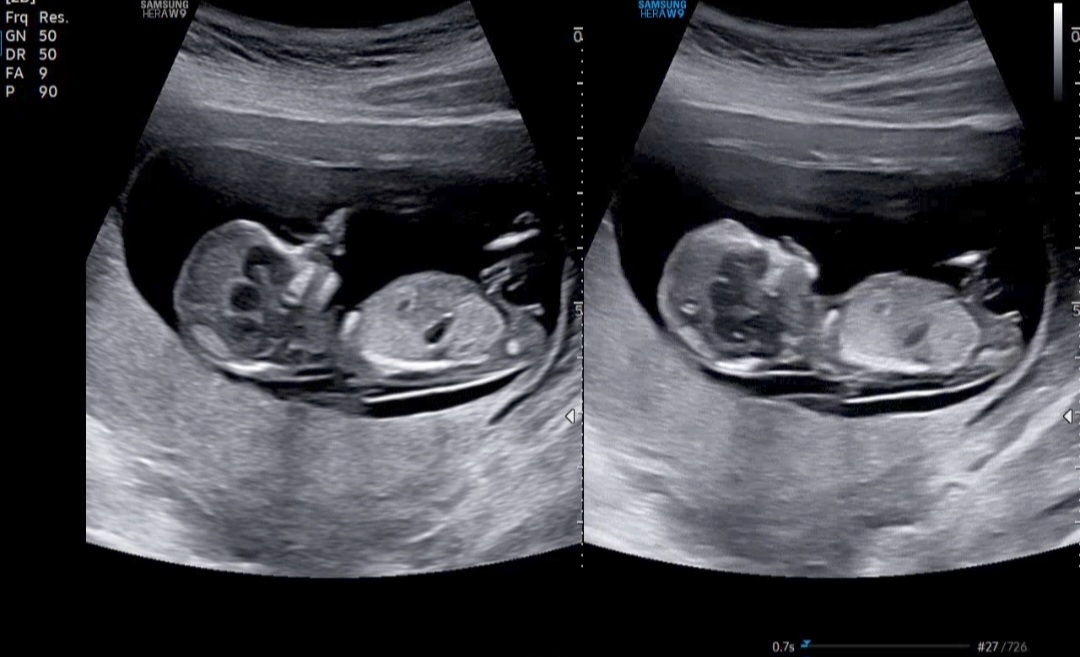

12주1일차에 정밀촘파 기형아검사하구 왔어요~~ 각도법 조언 부탁드려요🫶

딸같은데요?! 각도가 평행해보여요😖